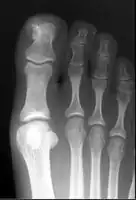

| Subungual exostosis (1/3), in a boy of 15 years old | |

Diagnosis involves medical imaging to exclude other similar conditions, particularly osteochondroma.[1][7] X-ray appearance may reveal a bony protuberance attached to the top or side surface of a toe bone, and it does connect to the medullary cavity.[2]

X-ray foot showing subungal exostosis